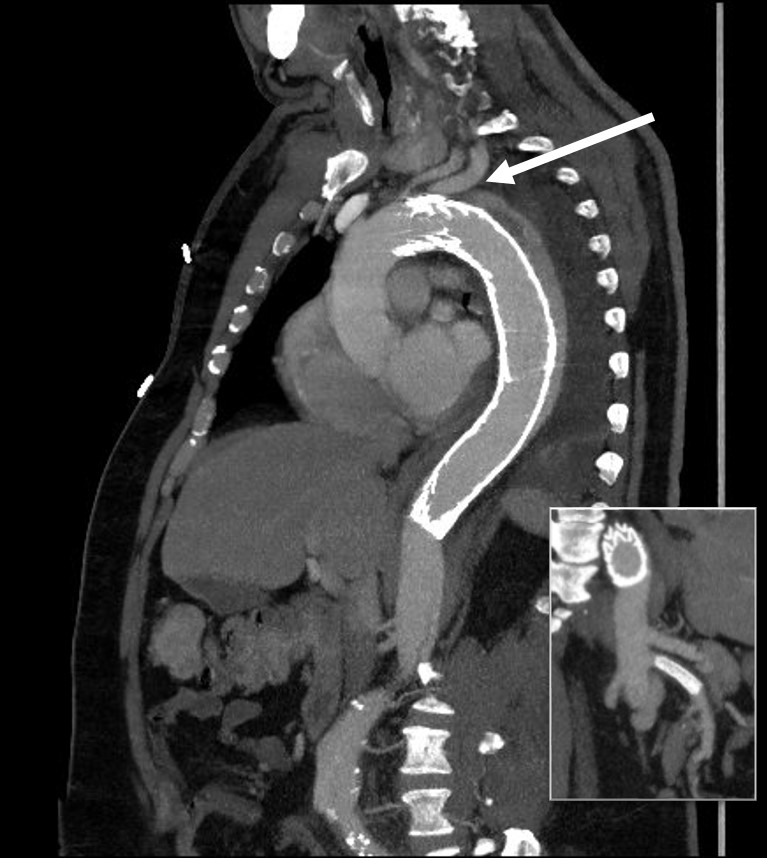

The patient is middle aged and had a type B thoracic aortic dissection (TBAD) as a consequence of recreational substances that acutely raised his blood pressure. At the outside hospital, he had a CTA showing the dissection extending from his left subclavian artery and causing occlusion of his superior mesenteric artery (SMA). He developed abdominal pain and was swiftly transported to our acute aortic syndrome unit. He was taken to the operating room and underwent a TEVAR of the dissection and stenting of his SMA -this is similar to other cases I have discussed in prior posts so I am omitting the technical details. The stent covered the left subclavian artery origin to exclude the origin of the dissection. The stent was extended to the distal thoracic aorta but did not go to the celiac origin.

Post procedure, his lactate never rose and he was maintained on the usual post procedure protocol of keeping MAP’s (mean arterial pressure) above 80mmHg. His left subclavian artery was covered but I do not routinely bypass, especially when the left vertebral artery is at least equal in size to the contralateral one. I don’t often place spinal drains for urgent/emergent cases particularly in patients who have never had infrarenal aortic surgery and patent hypogastric arteries. He was kept sedated overnight and awoke in the morning unable to move his legs to command. He had no pain sensation up to his umbilicus.

A spinal drain was emergently placed and his blood pressure was raised to MAPs of 90+, but these failed to reverse his paralysis. After discussion among my world class partners, I chose to take the patient back for a carotid subclavian bypass which was done through a single incision with a dacron bypass graft.

His paralysis resolved. He was discharged home, ambulating without assistance. Spinal cord complications are reported to occur between 1-5 percent of patients undergoing TEVAR for complicated TBAD. They were seen in 2 of 72 patients in the TEVAR arm of the INSTEAD trial (Circulation, 2009 vol. 120(25) pp. 2519-28), and was permanent in 1. While there are some who routinely place prophylactic drains, it is unclear to me that they have a significant effect if placed unselectively. I will place a Preop drain in the instance of infra renal graft, hypogastric arterial occlusive disease. In the instance of a dominant left vertebral, I will perform concomitant bypass, but just as often not. This is a gratifying and rare outcome of paralysis reversed with a carotid subclavian bypass when spinal drain and permissive hypertension did not.